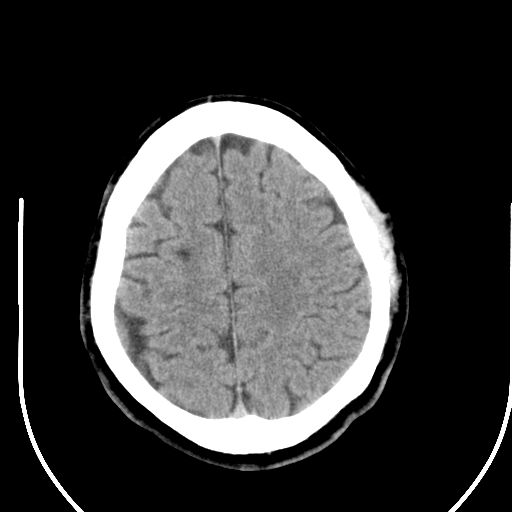

标题: CT25423:头部外伤意外发现右顶叶??? [打印本页]

标题: CT25423:头部外伤意外发现右顶叶???

ct值约13hu。

边缘清晰,没有占位效应,不像脑沟,结合ct值,软化灶可能吧

与脑沟没关系,小软化灶或陈旧性感染吧!

看样年纪不小了直接报腔梗,当然你要想报软化灶也是一样的

考虑右侧额叶巨腔隙灶;建议必要时行mri检查。